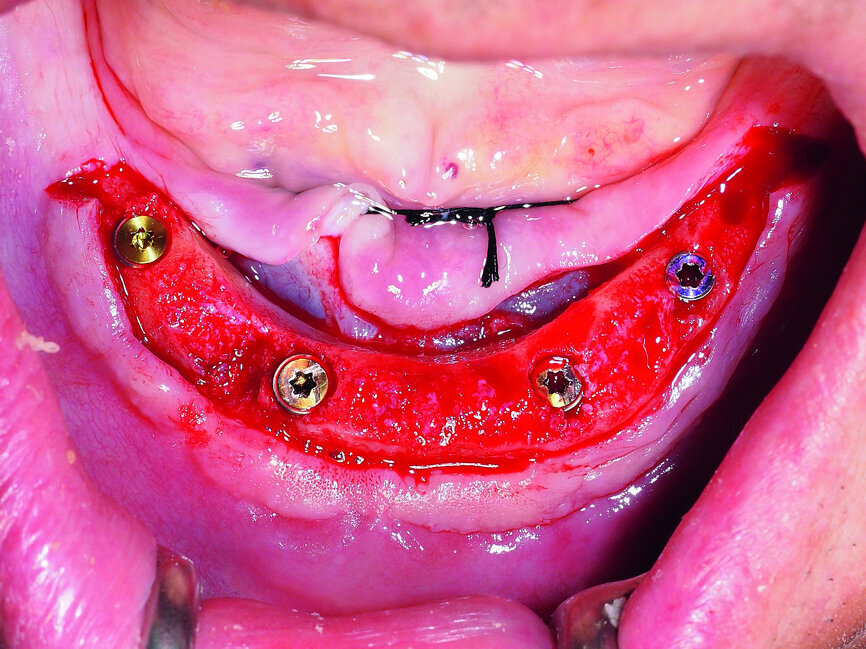

Fig. 2: Placement of four GC Aadva implants in the interforaminal region.

Regarding the occlusion-related factors, it is important to note that the implant placement should be precise and prosthodontically driven, bearing in mind the biomechanics of the final restoration. This means minimising the adverse leverage loads by centring implants in the mesiodistal plane, placing them perpendicular to the occlusal plane, choosing key implant positions and avoiding cantilevers (Figs. 1 & 2).[24] Moreover, the occlusion must be well-balanced with particular regard to patients with high masticatory forces and parafunctional habits.